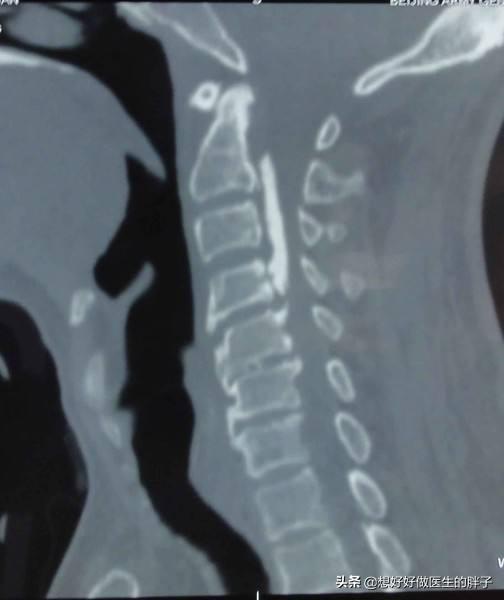

而x线检查可以明确颈椎椎体是否有严重的骨质增生,曲度是否有改变,对于某一些严重骨质增生的颈椎病患者,还建议患者进行三维ct检查,明确椎管内是否有明显的后纵韧带钙化,下图白色的高亮区域就是钙化的韧带,这么长,这么严重的钙化,患者的神经肯定会受到压迫。